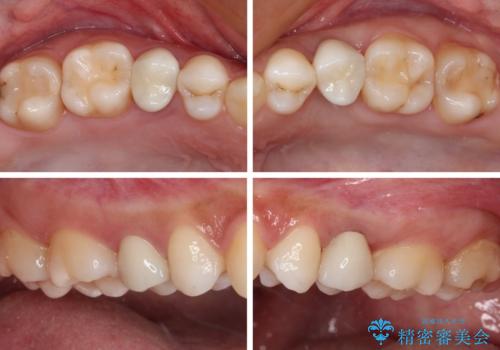

まずは虫歯を除去した上で根管治療を行い、部分矯正により骨内深い位置にまで及んだ健全な部分を引っ張り出すこととしました。

その後骨形成処置を行い、治癒を待って補綴治療を行うこととしました。

かなり深い位置にまで虫歯が及んでいたため、かなりの量を引っ張り出す必要があり、残された歯根は短く小さい状態となりました。

今後も定期的にレントゲンを撮るなど、経過を追っていく必要があります。